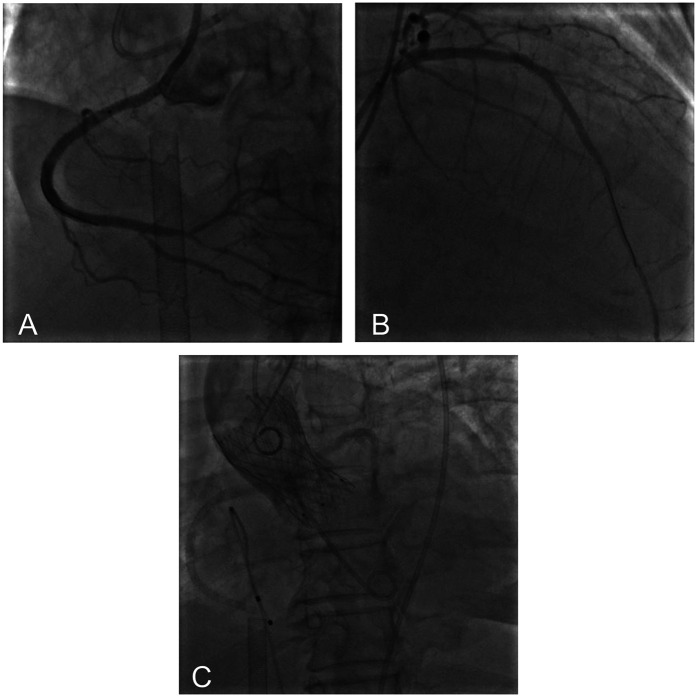

主动脉瓣狭窄(AS)经常与冠状动脉疾病(CAD)相关,特别是在治疗策略缺乏标准化临床指南的高危患者中。我们报告了一例严重AS和高危CAD患者,导致严重的心力衰竭,手术主动脉瓣置换术和冠状动脉搭桥术不适合,因为发病率和死亡率非常高。患者接受了体外膜氧合(ECMO)辅助经导管主动脉瓣置换术(TAVR)和经皮冠状动脉介入治疗(PCI)的一站式手术。术中患者先行预防性静脉-动脉ECMO置管,成功行右冠状动脉和左前降支PCI,然后行TAVR,无并发症。患者对手术的耐受性良好,血流动力学在整个过程中保持稳定。在一年的随访中,患者的心功能明显改善。本病例为治疗高危AS合并CAD提供了宝贵的经验,证明了该方法在临床实践中的可行性和有效性。

Aortic stenosis (AS) is frequently associated with coronary artery disease (CAD), particularly in high-risk patients for whom treatment strategies lack standardized clinical guidelines. We report a case of a patient with severe AS and high-risk CAD, leading to significant heart failure, for whom surgical aortic valve replacement and coronary artery bypass grafting were unsuitable because of very high risk of morbidity and mortality. The patient underwent a one-stop procedure combining extracorporeal membrane oxygenation (ECMO)-assisted transcatheter aortic valve replacement (TAVR) and percutaneous coronary intervention (PCI). During the procedure, the patient first received preventive veno-arterial ECMO placement, successfully underwent PCI on the right coronary artery and left anterior descending artery, and then TAVR was performed without complications. The patient tolerated the procedure well, with hemodynamics remaining stable throughout. At one-year follow-up, the patient's heart function was significantly improved. This case provides valuable experience in treating high-risk AS combined with CAD, demonstrating the feasibility and effectiveness of this approach in clinical practice.